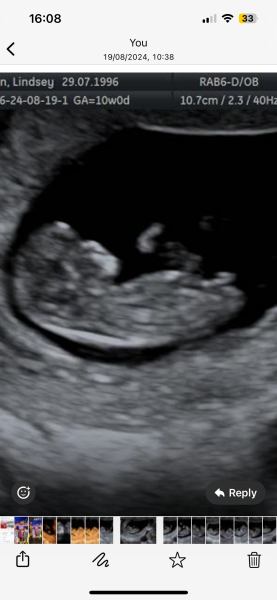

Hi guys I’ve been for my scan and I was 10 weeks and 4 days any idea on gender based off nub theory I have been told that during 10-12 weeks the nub can look relatively the same both boy and girl , but any ideas?